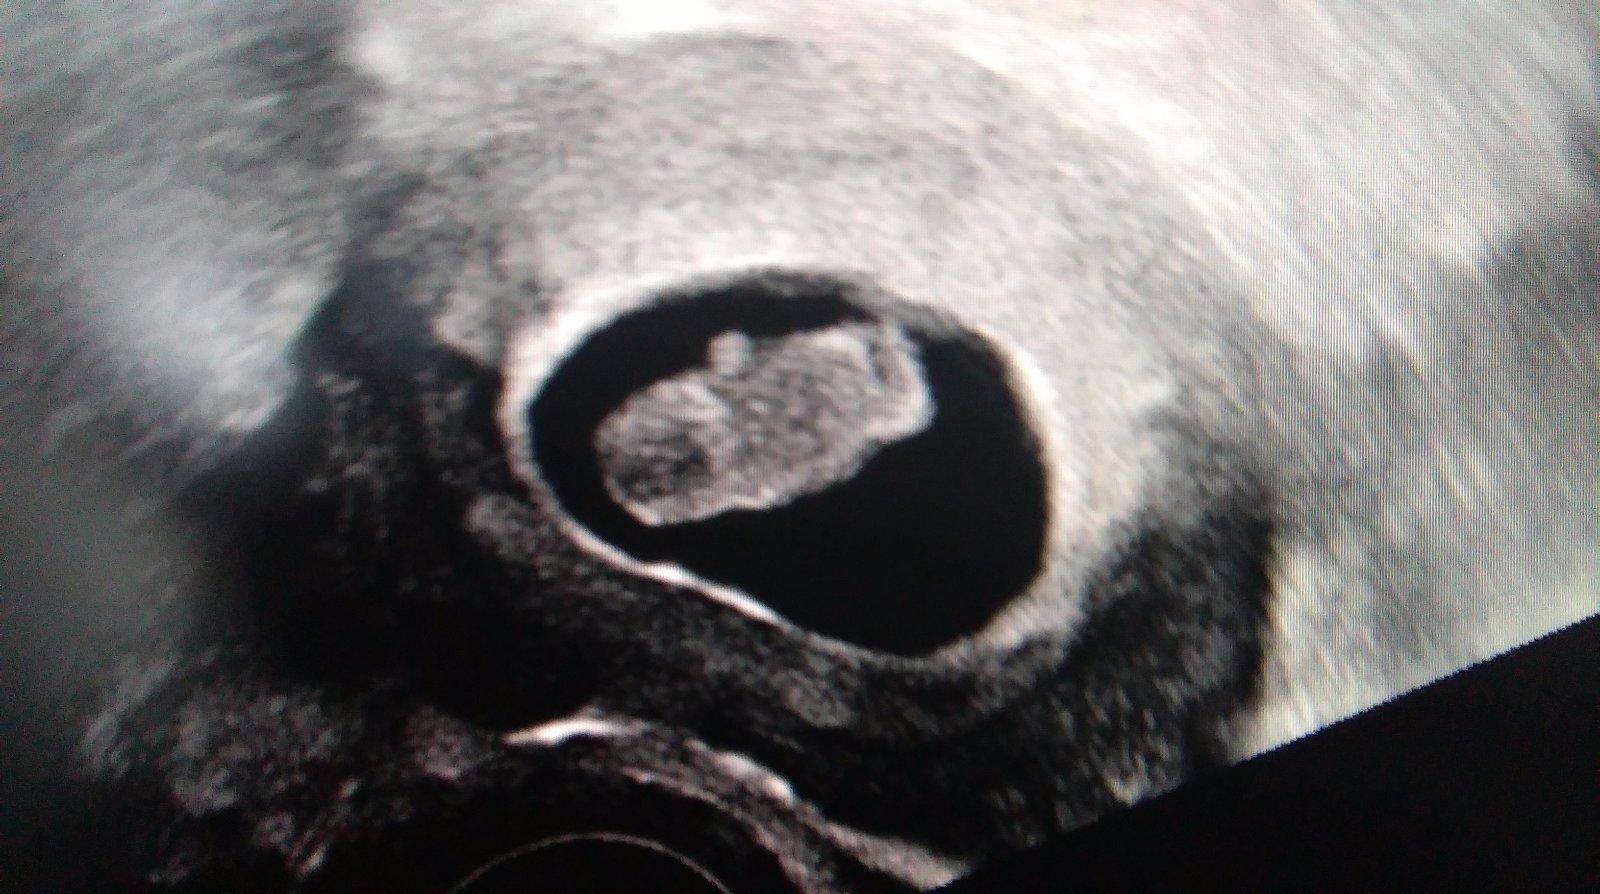

Moje mrňo 😊

@agathachristie jeeeeeeej ako krasne ho vidieeeeet 😵 😵

Nadherna fotecka juuj 🙂